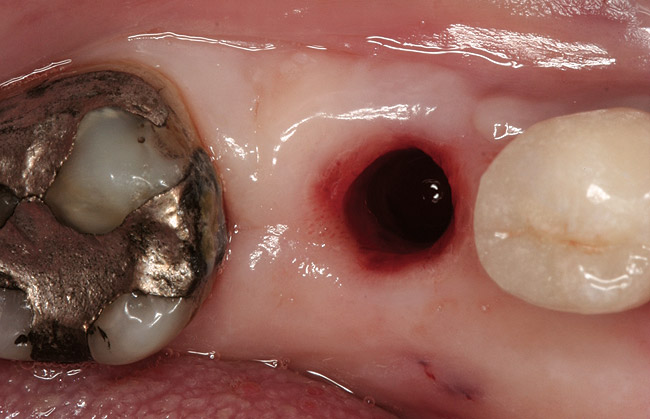

Figure 1  Periapical radiograph of a failed implant with peri-implantitis. Bleeding on probing and pus from the mesial pocket was present.

Figure 1

Figure 2  Following crown and abutment removal, the implant platform was exposed.

Figure 2

Figure 4  The site following atraumatic implant removal.

Figure 4